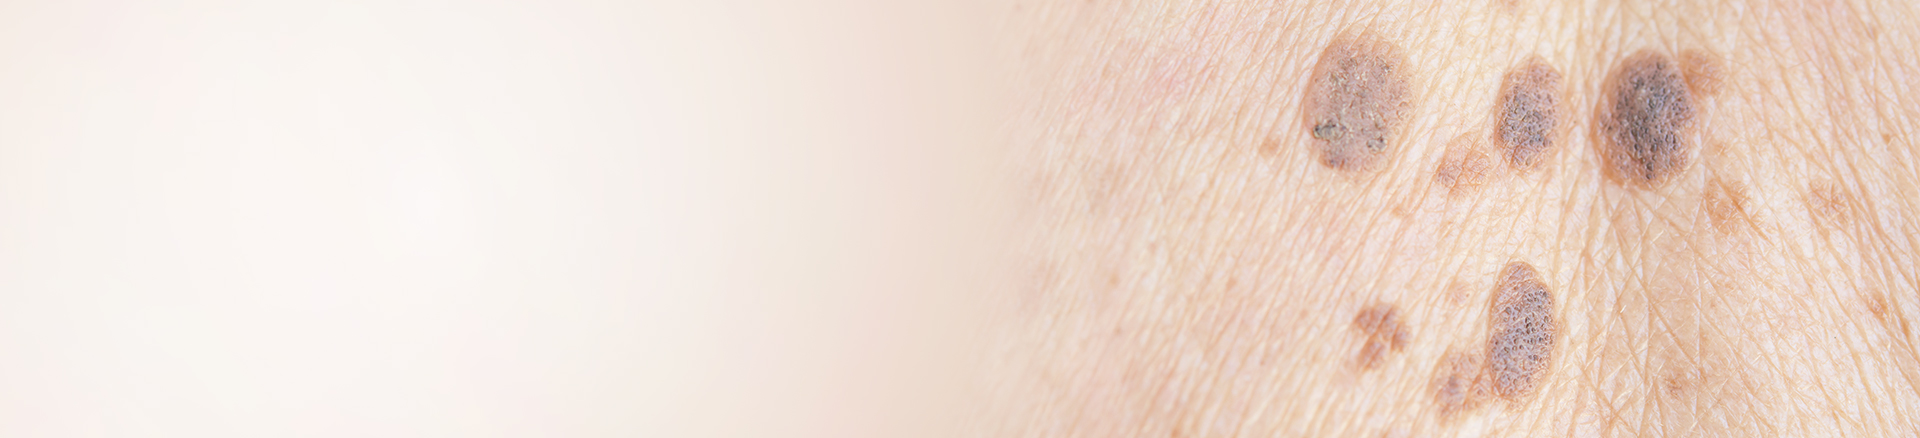

Skin Cancer Pictures

Early detection of skin cancer can help improve outcomes. Skin cancer pictures can give you an idea of the types of spots, bumps, sores and moles to monitor. Sores that do not heal, scaly patches that are not associated with psoriasis or eczema, irregular moles, rapidly changing spots and other abnormalities should be evaluated as soon as possible. Regular skin checks should be performed monthly. Check all visible parts of your body, and use a mirror or ask a partner or friend to check those hard-to-see areas, such as your back.

Although skin cancer can affect people of all ages and from all backgrounds, you may be at a higher risk if you have fair skin, naturally light hair or eyes, you tend to freckle or burn easily, you have a history of severe sunburns as a child, you work or otherwise spend considerable time in the sun or you live in a warm, sunny climate. You may also be at a higher risk if you have many moles or several abnormal moles, which tend to be larger than normal moles and irregularly shaped. Skin cancer pictures can be a great way of knowing what you need to look for, but only a dermatologist can provide you with an accurate diagnosis.